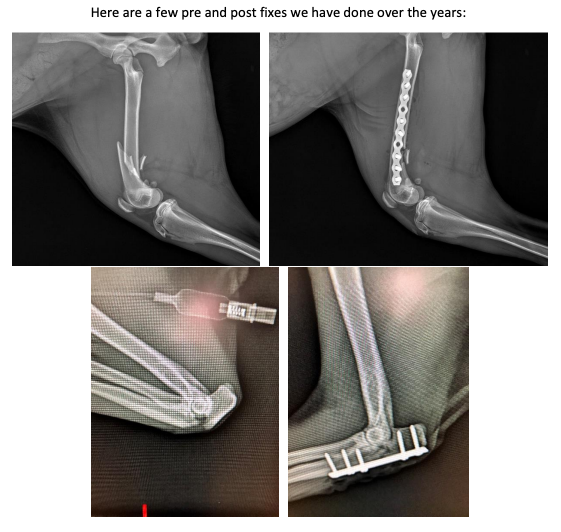

tta picture

Pet Tta Surgery

Canine Knee Surgery – Healing your Dog’s Knee Injury

Tibial Tuberosity Advancement to Repair your Dog’s Cranial Cruciate Ligament Injury, with the Least Discomfort and Stress to your Dog.